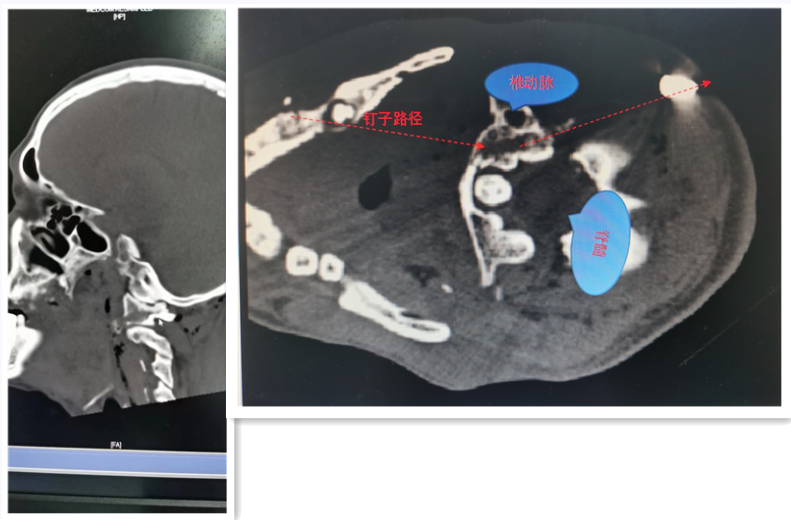

经查体并结合患者随身携带的影像资料,钉子从患者口唇穿入,击碎牙齿,经咽喉,击穿寰椎侧块,紧贴着延髓(生命中枢,控制呼吸和心跳)和椎动脉,最终从左枕后穿出于皮下。

因患者自带的头面部CT胶片未能明确钉子的确切位置,为明确钉子的具体位置和周围重要结构的关系,骨科医师立即安排患者进行寰枢椎CT检查。

CT结果显示寰椎骨折

CT结果显示,患者口腔中多个牙齿断裂及左侧寰椎侧块骨折,异物位于左颈后,部分穿出体外。